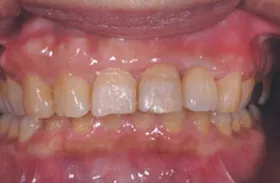

■治療前:生まれつき下顎左右前歯がなく隙間がある

■治療後:矯正治療後、下顎左右3番の2本にインプラント治療

| 主訴 | 生まれつき歯がなく隙間があり、審美障害・咀嚼機能障害がある |

| 治療方法 | インプラント治療 + 矯正治療 |

| 治療期間 | インプラント治療 約6ヶ月 |

| 通院回数等 | インプラント治療 約6回 |

| 費用 | 約94万円(税込) |

| リスク・副作用 | 術後の腫れ・痛み |